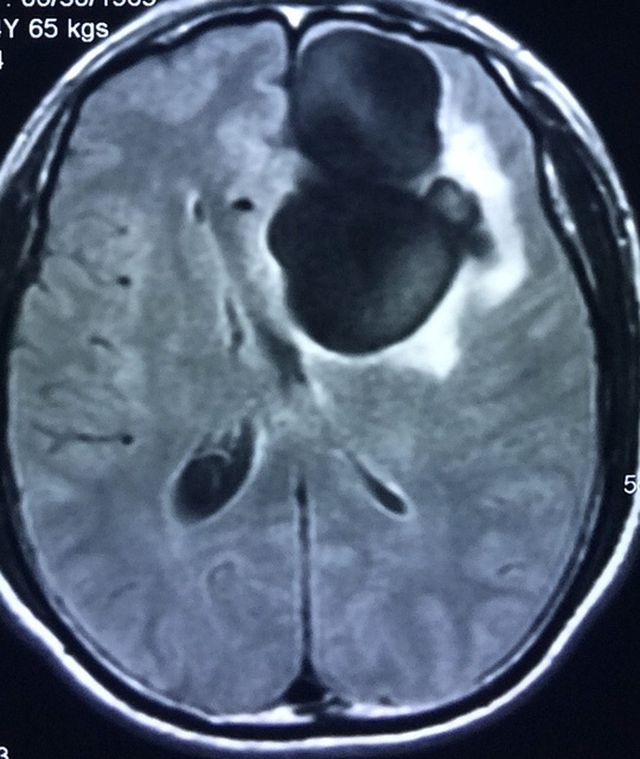

Trước đó khoảng 2 tuần, bệnh nhân vốn luôn "khoá khẩu" món tiết canh có dấu hiệu đau đầu, choáng váng, sốt, lên cơn co giật. "Tại thời điểm nhập viện, bệnh nhân hôn mê. Kết quả chụp cắt lớp vi tính phát hiện bệnh nhân có một khối u lớn trong não dạng nang, nghi ngờ trong não có nang sán hoặc khối u.

Với những bệnh nhân tỉnh táo, bác sĩ sẽ chụp cộng hưởng từ để đánh giá kết quả chính xác hơn nhưng do bệnh nhân đã hôn mê nên được chỉ định mổ ngay lập tức. Kết quả, khi mổ ra các bác sĩ phát hiện một tổ nang sán lớn như chùm nho có kích thước 5 cm x 6 cm làm tổ trong não. Sau mổ, bệnh nhân phải hồi sức 3 ngày mới tỉnh trở lại và được điều trị tích cực" - bác sĩ Liên nói.

Trước đó 1 tuần, cũng Khoa ngoại thần kinh đã tiếp nhận bệnh nhân nam 54 tuổi, ở Hà Giang, nhập viện trong tình trạng đau đầu, hay quên. Kết quả chụp cộng hưởng từ cho thấy bệnh nhân có nang sán dây lợn trong não kích thước 4x5 cm. Bệnh nhân có thói quen ăn tiết canh, rau sống.